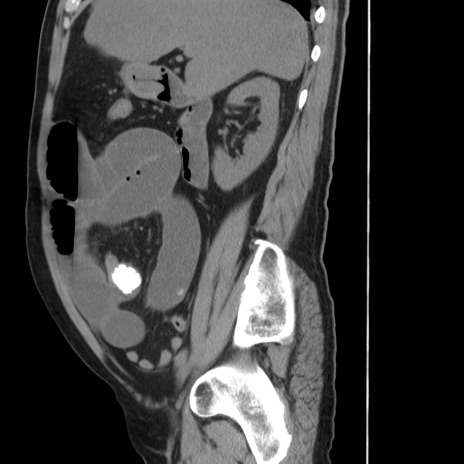

症例20(矢状断像)

【症例】 60歳代男性

【主訴】 腹部膨満、嘔吐

【現病歴】5日前頃より倦怠感を認め食事量減少し4日前の朝嘔吐、食事摂取困難となった。 3日前近医受診し点滴施行され整腸剤などを処方された。 当日他院を受診し、腹部膨満著明、炎症反応の上昇(CRP10.8、WBC11200)あり、紹介受診となる。

【身体所見】 意識JCS1 受け答えがはっきりしないBP 111/57mHg、 P 67bpm、、BT35.2°C、SpO2 97%(RA)、 腹部:膨隆、打診で鼓音あり、全体的に圧痛有り、腸蠕動音(-)、反跳痛ははっきりせず。

【データ】WBC 11400、CRP 14.20

冠状断像